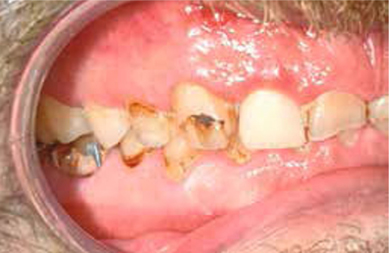

Afb. 5

Lateraal aanzicht rechts.

Bij het extraoraal onderzoek zie ik een lichte hypertrofie van de m. masseter. Intraoraal tref ik een ernstig versleten dentitie aan waarbij de slijtage niet passend bij de leeftijd kan worden genoemd (afbeelding 2-7 en tabel 1) .